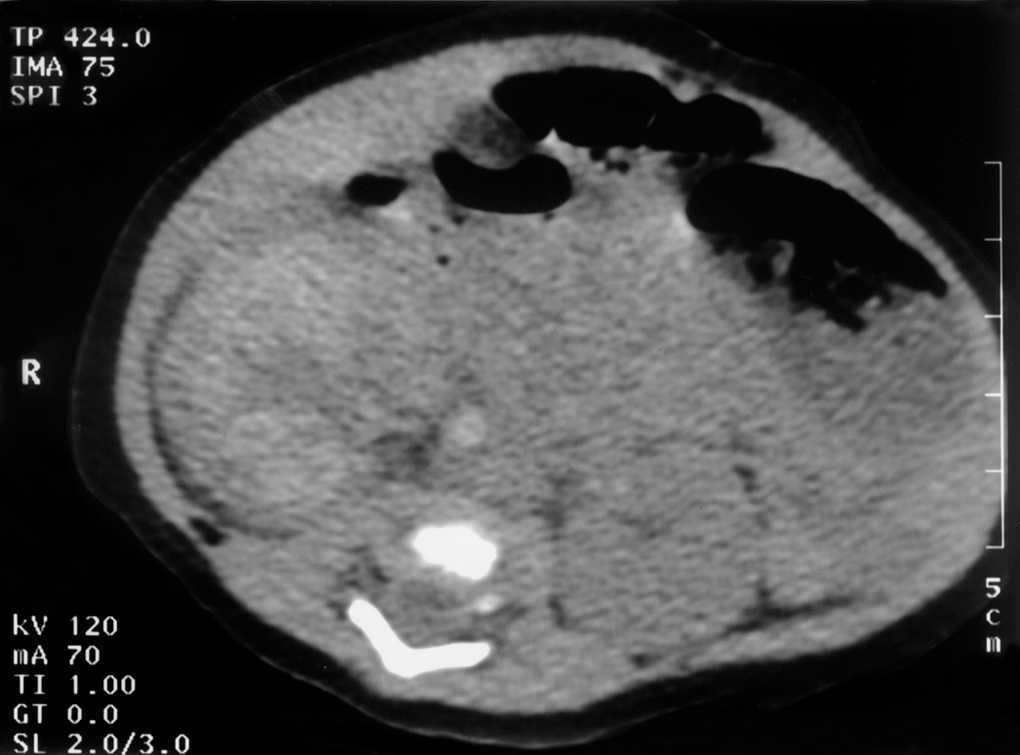

Figura 3.TC abdominal: calcificación de la vena cava inferior infrarrenal compatible con trombosis.